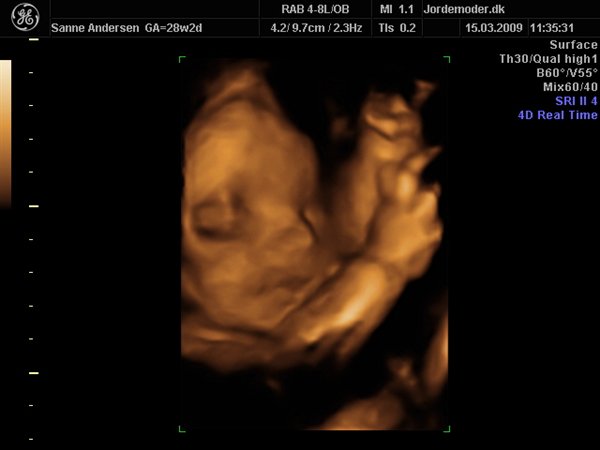

Det gik bare så godt til scanningen, men den ville meget heller sove end være aktiv så vi kunne få en masse forskellige billeder... men vi har fået en masse dejlige billeder og en dvd hvor der er masser af hjertelyd og rigtig pænt billede af hvordan hjertet slår

men vi venter en lille dreng, vi kunne desværre ikke få billede i 3d da han bare ikke ville rykke på sig og han lå så der var for meget fostervand...

Vedhæftede fotos (klik for at se i fuld størrelse)